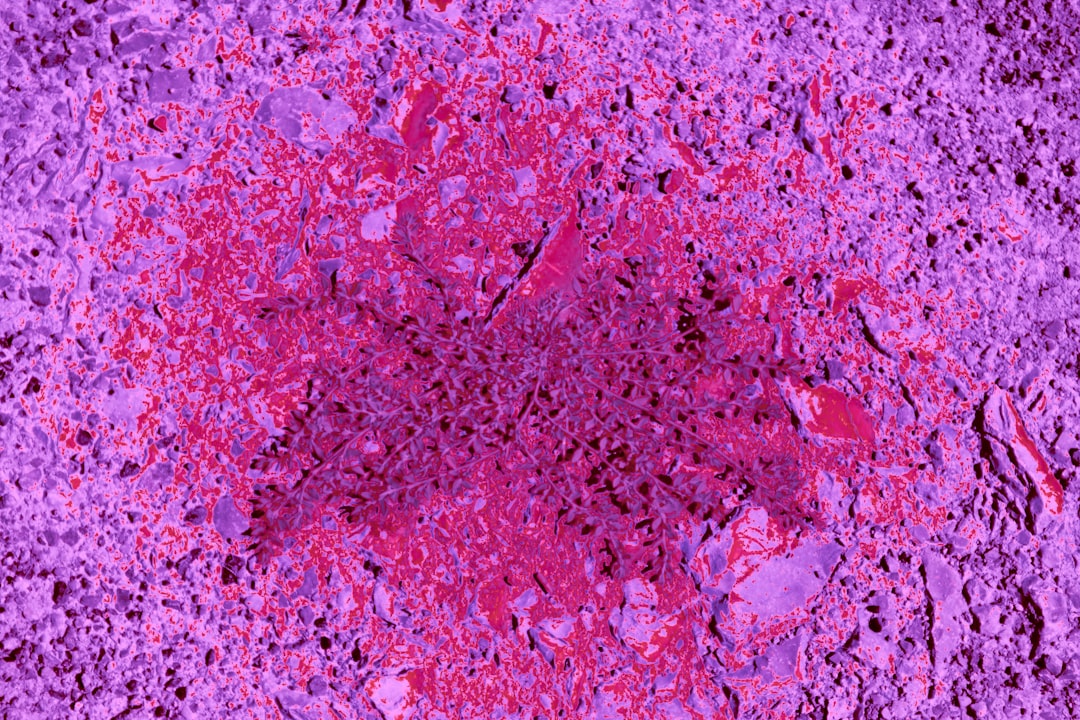

대장암 의심 증상으로는 다른 증상들도 다양하게 존재합니다. 이러한 증상들은 보통 대장 내에서의 이상 소견을 바탕으로 합니다. 간혹 대변에 혈액이나 점액이 섞여 나오는 경우가 있는데, 이것은 결코 가벼운 증상이 아닙니다. 실제로 제 주변에서 이러한 증상을 겪었던 지인이 있었는데, 초기 검사로 인해 조기에 대장암이 발견되었습니다. 모두가 이처럼 본인에게 소중한 시간을 소홀히 하지 않도록 하길 바랍니다.